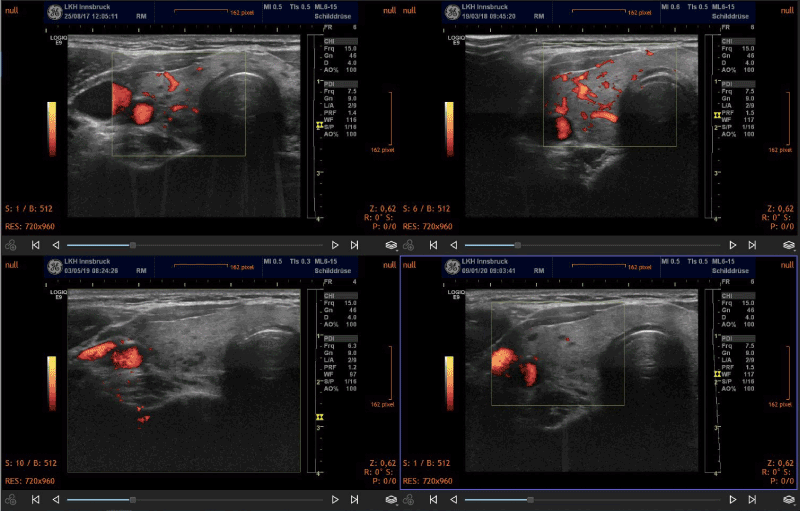

Over a period of 18-24 months, signs of improved morphology and decreased vascularization were seen. In general, the morphological changes included a reduction of thyroid volume and a normalization of the structure of the gland in cases of subacute thyroiditis. Two representative clinical cases are shown in the figure 1. In hyperthyroidism the pattern of increased vascularization of the gland normalized during treatment (Figure 2). Thyroid morphology also showed improvement (Figure 3).

Figure 2. Sequential demonstration of normalization of thyroid perfusion in a case of Grave’s disease. The initial studies (upper panel) revealed enlarged vessels which correspond to CoQ10 deficiency. Following supplementation vascularization returned to normal.